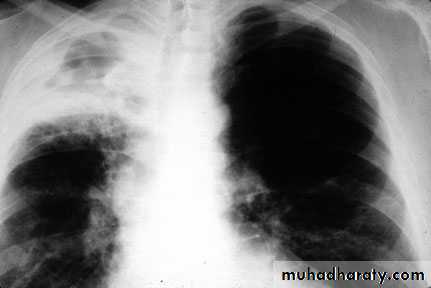

• Pulmonary TB

Cough, fever, upper lobe pulmonary infiltrateCough, fever, any pulmonary infiltrate in an HIV-infected patient (or patient at risk for HIV infection)

Tuberculosis, pulmonary or

laryngeal